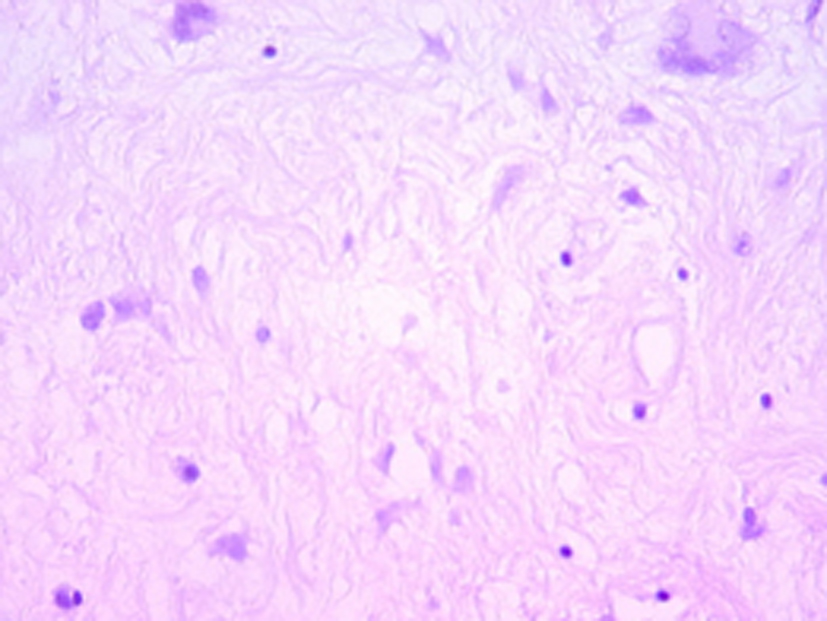

Histologically, the tumor was well circumscribed, of moderate cellularity, composed of bland spindle or plump cells dispersed in a loose-textured and myxoid stroma (Fig. 2). The cytoplasm was eosionophilic or amphophilic without cross-striations. The nuclei were round or elongated, with dispersed chromatin and inconspicuous nucleoli. Multinucleate histiocytoid cells with an eosinophilic or vacuolated cytoplasm were also seen (Fig. 2). The tumor cells were intermingled with an inflammatory infiltrate consisting of plasmocytes, small lymphocytes and occasional eosinophils. Nuclear atypia, mitoses and foci of necrosis were not identified. Immunohistochemically, the tumor cells were consistent with a myofibroblastic phenotype; they expressed strongly vimentin (1 : 100; Dako, Glostrup, Denmark) and smooth muscle actin (1 : 100; Dako) (Fig. 3). Cytokeratin (1 : 75; Dako) and PS100 (1 : 50; Dako) were negative. There was no expression of anaplastic lymphoma kinase ALK (1 : 50; Dako) protein. A marked overexpression of protein p53 (1 : 25; Dako) by tumor cells was found (Fig. 4). Special stains for mycobacteria and fungi were negative. In situ hybridization (PNA probes, Dako) performed to detect Epstein-Barr virus (EBV) was negative. Investigation of Human Herpesvirus-8 (HHV8) by polymerase chain reaction (PCR) was also negative. The histological diagnosis was of an inflammatory myofibroblastic tumor of the retro peritoneum.

![]() Click for large image | Figure 2. Hematoxylin-eosin x 200: bland fusiform and multinucleate cells admixed with inflammatory cells, mainly lymphocytes within a myxoid stroma. |